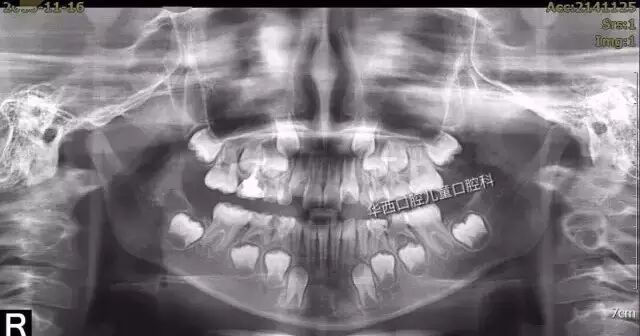

拍出来的时候就是这样的。(图片据微博)

来看,这幅全景片就是一个混合牙列期的小朋友。纳尼?这个5、6岁的小孩骨头里怎么还有一副牙齿?是的,你眼睛没看花,孩子们在这个时候牙齿就是这么奇怪,乳牙还没还没掉,恒牙已经在牙周膜(那个小圈圈)的保护下在牙槽骨里蓄势待发了!多说一句,这也是为啥乳牙掉了不补,就会殃及恒牙的原因了。可怜的恒牙在骨头里就躺枪了。。。。